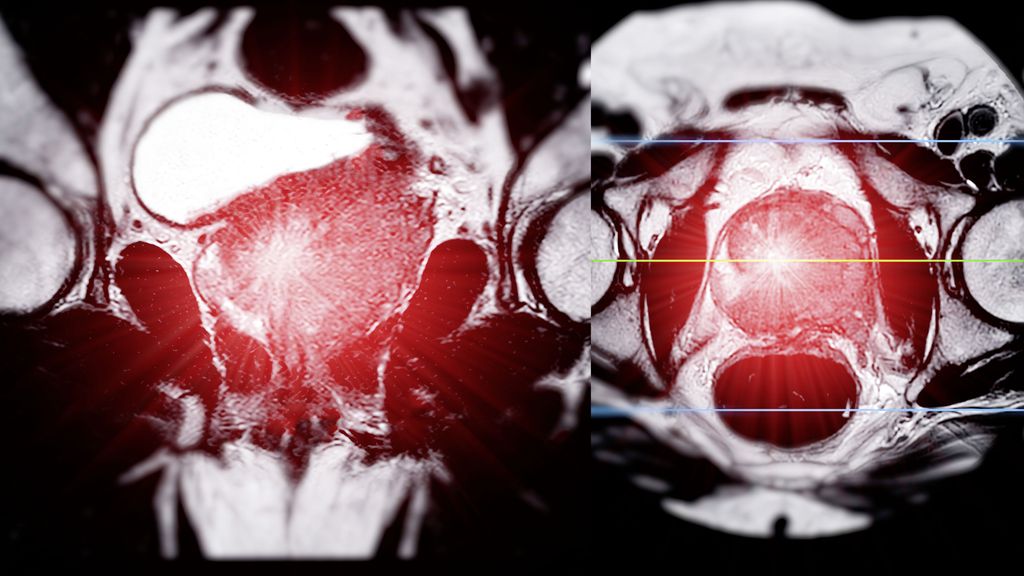

Die Therapielandschaft des fortgeschrittenen Prostatakarzinoms hat sich seit 2014 und damit der ersten Präsentation der CHAARTED-Studie praktisch jährlich verändert und erweitert. Heute ...